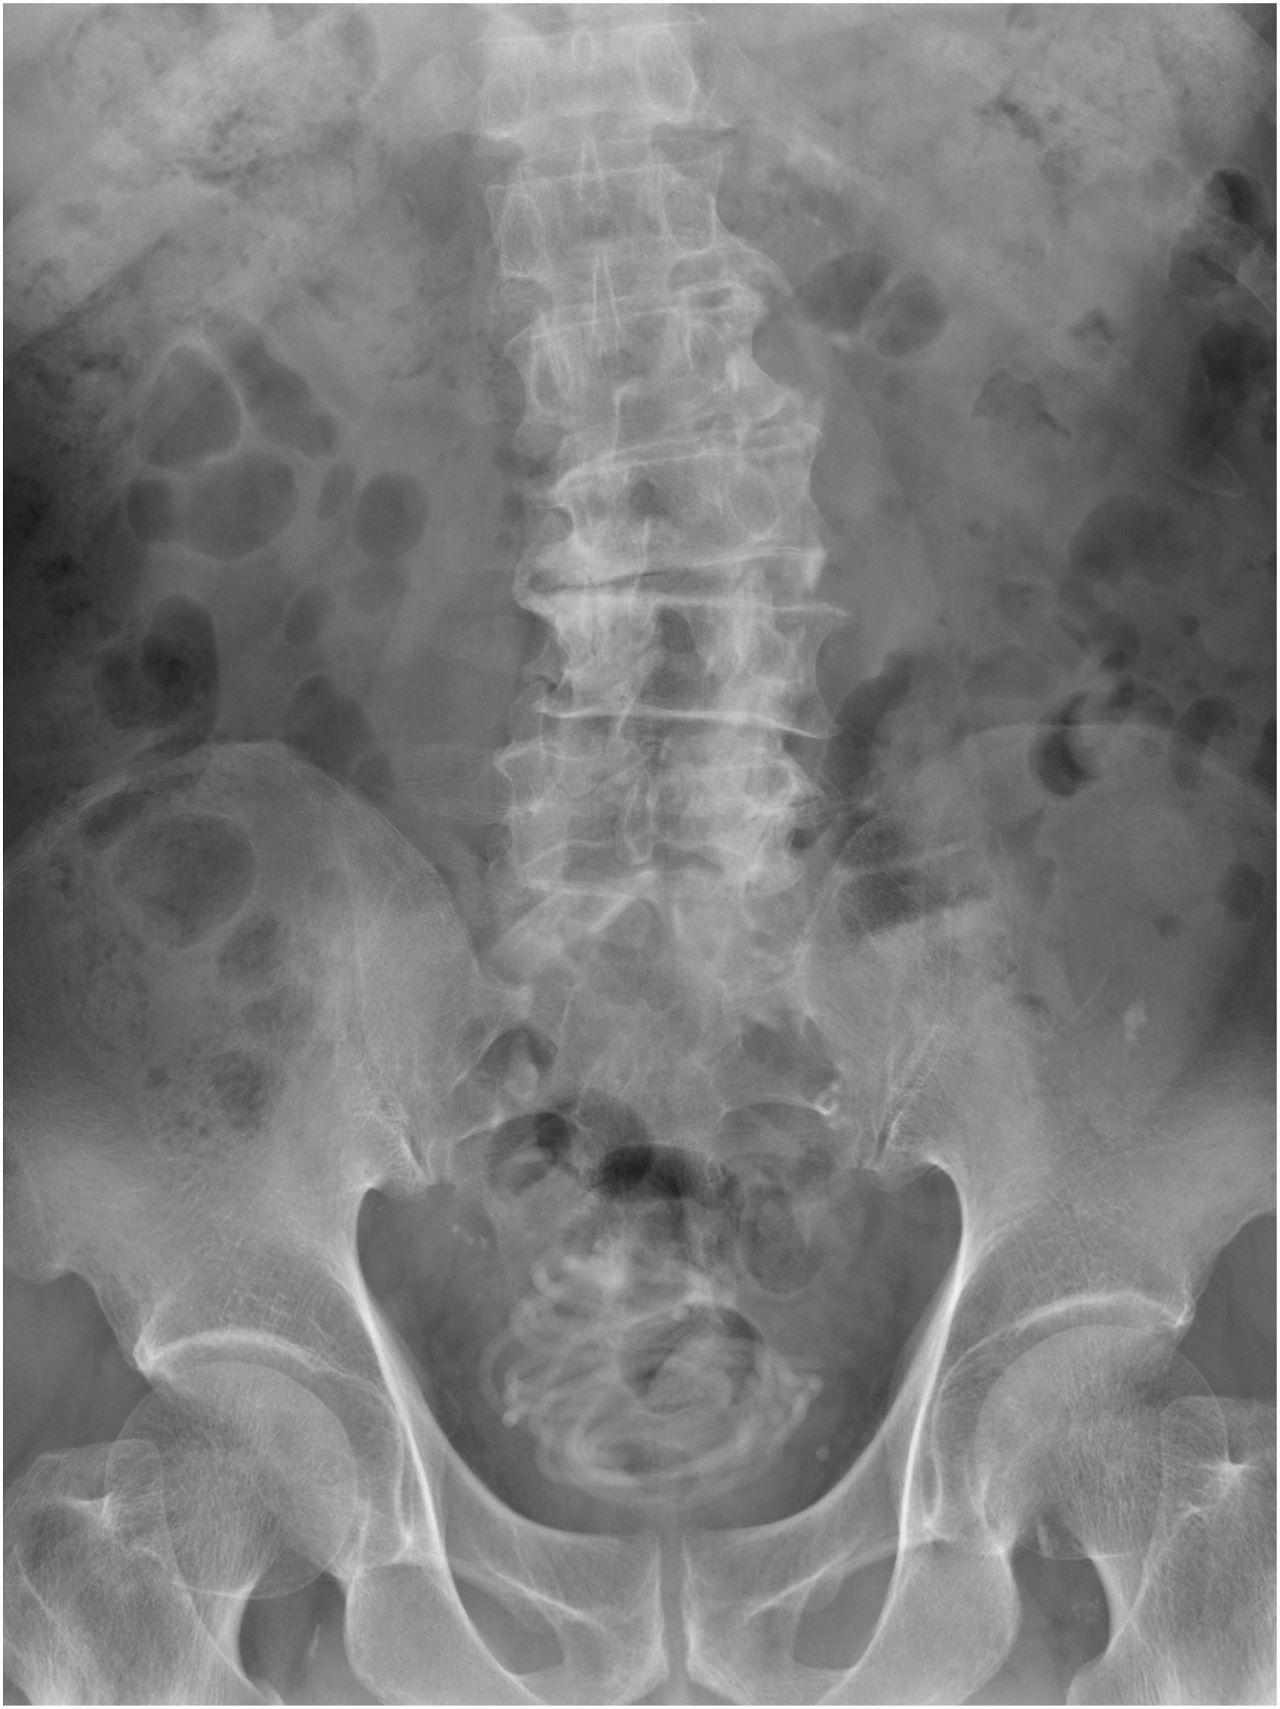

raio-x mostra corda dentro de bexiga de paciente

Legenda: Exames de imagem mostraram que a corda estava na bexiga do paciente

Médicos encontraram uma corda de pular na bexiga de um homem de 79 anos. O idoso procurou atendimento médico relatando sentir dores ao urinar. Depois da realização dos exames de imagens, a equipe médica se assustou ao encontrar o objeto, que tinha 2,3 metros de comprimento

“Primeiro realizamos um ultrassom e identificamos um objeto grande na bexiga do paciente. Depois fizemos um raio-x, que revelou um corpo estranho enrolado em forma de fio. Em seguida, fizemos uma tomografia que nos ajudou a escolher o melhor jeito de tirar a corda e usamos um programa de computador em 3D para nos direcionar. Percebemos que seria impossível puxar a corda pelo pênis”, disse Toshiki Kijima, professor de urologia na Dokkyo Medical University, autor do documento.